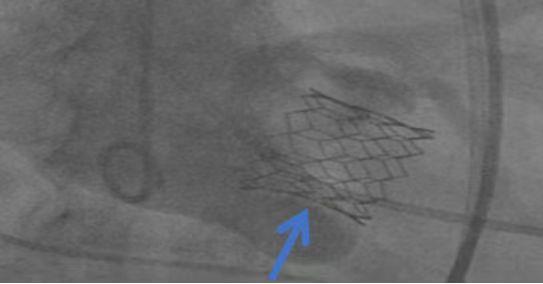

植入的心脏瓣膜

在征得患者及家属同意后,罗裕主任和汤勇副主任团队,耗时仅1.5小时就顺利为患者完成了手术。术后,患者恢复良好。据了解,此例手术为RENATUS?心脏瓣膜(我国自主研发的经导管主动脉瓣系统)上市之后全国首批植入。